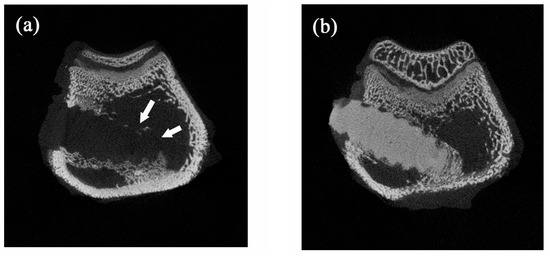

When the bone screws were placed in the rabbits for four weeks, new bone formation at the implant/bone interface was observed both in nano-Fe3O4/PLLA group (Figure 7a) and neat PLLA group (Figure 7b). Furthermore, along with the degradation process, bone tissue grew into the nano-Fe3O4/PLLA screw at the bone interface between threads. Leached nano-Fe3O4/PLLA debris was surrounded by bone tissue without an observable inflammatory response or side effect (Figure 7a). Figure 8 shows typical micro-CT images of the implanted bone screws. The neat PLLA screws showed no radiopacity and could not be distinguished from the surrounding tissue (Figure 8a). However, the addition of 20% nano-Fe3O4 particles significantly improved the radiopacity of the PLLA screw. The boundary and location of the 20% nano-Fe3O4/PLLA screw were easily identified without any blooming artifact (Figure 8b).

Researchers have added various contrast agents to enhance the radiopacity of polymeric devices. Most investigators reported that these compounds reduced the thermal stability of the polymer [11,28,29]. However, our results showed a different trend. The addition to Fe3O4 nanoparticles improving not only the radiopacity of the PLLA (Figure 8b) but also increasing the thermal stability of the polymer. Figure 4 and Table 1 show that the highest decomposition temperatures occurred when 20% Fe3O4 nanoparticles were incorporated into the PLLA. This result is consistent with the report by Rakmae et al. (2011). They found that the addition of filler to the PLLA increased the thermal decomposition temperatures (Tonset) of the composite compared with that of the neat polymer [30]. They reported that the thermal stability of the PLLA composite was due to the thermally stable filler, which decreased the decomposition of the polymer. These additives may act as barriers to prevent heat transfer [30]. This improvement also contributes to the interface interaction between the nanoparticles and the PLLA [31]. However, the composites containing 30% or 40% Fe3O4 have lower thermal decomposition temperatures than that of 20% samples. It may be due to the decrement of molecular weight during mixing with a higher ratio of inorganic filler [32]. The addition of 20% nano-Fe3O4 particles provided the best dispersion and distribution of nano-Fe3O4 particles in the PLLA.

The CT image shown in Figure 8b demonstrated that the addition of nano-Fe3O4 particles at 20% provided excellent X-ray visibility. These findings are consistent with previous reports that the addition of 20% contrast agent to polymers provided optimal X-ray visibility without altering the physical properties of the polymer [29,33]. Thus, it is reasonable to suggest that the 20% nano-Fe3O4/PLLA has optimal thermal stability as well as radiopacity. However, the bending strength of this composite is still not large enough for use in weight-bearing areas. It only can be used in non-weight-bearing areas.

Figure 8. Typical micro-CT images of (a) neat PLLA screw and (b) 20% nano-Fe3O4/PLLA screw implanted in rabbit bone. The addition of 20% Fe3O4 nanoparticles significantly improved the radiopacity of the PLLA screws.